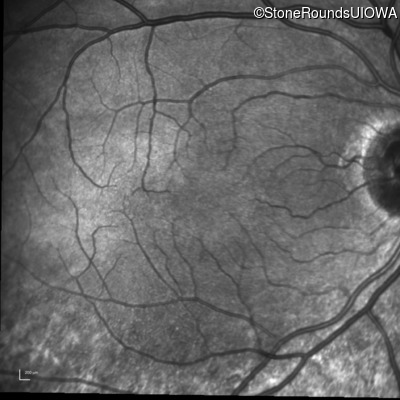

Infrared Fundus Photograph - Right - 20/20 -3

Infrared Fundus Photograph - Left - 20/20 -2